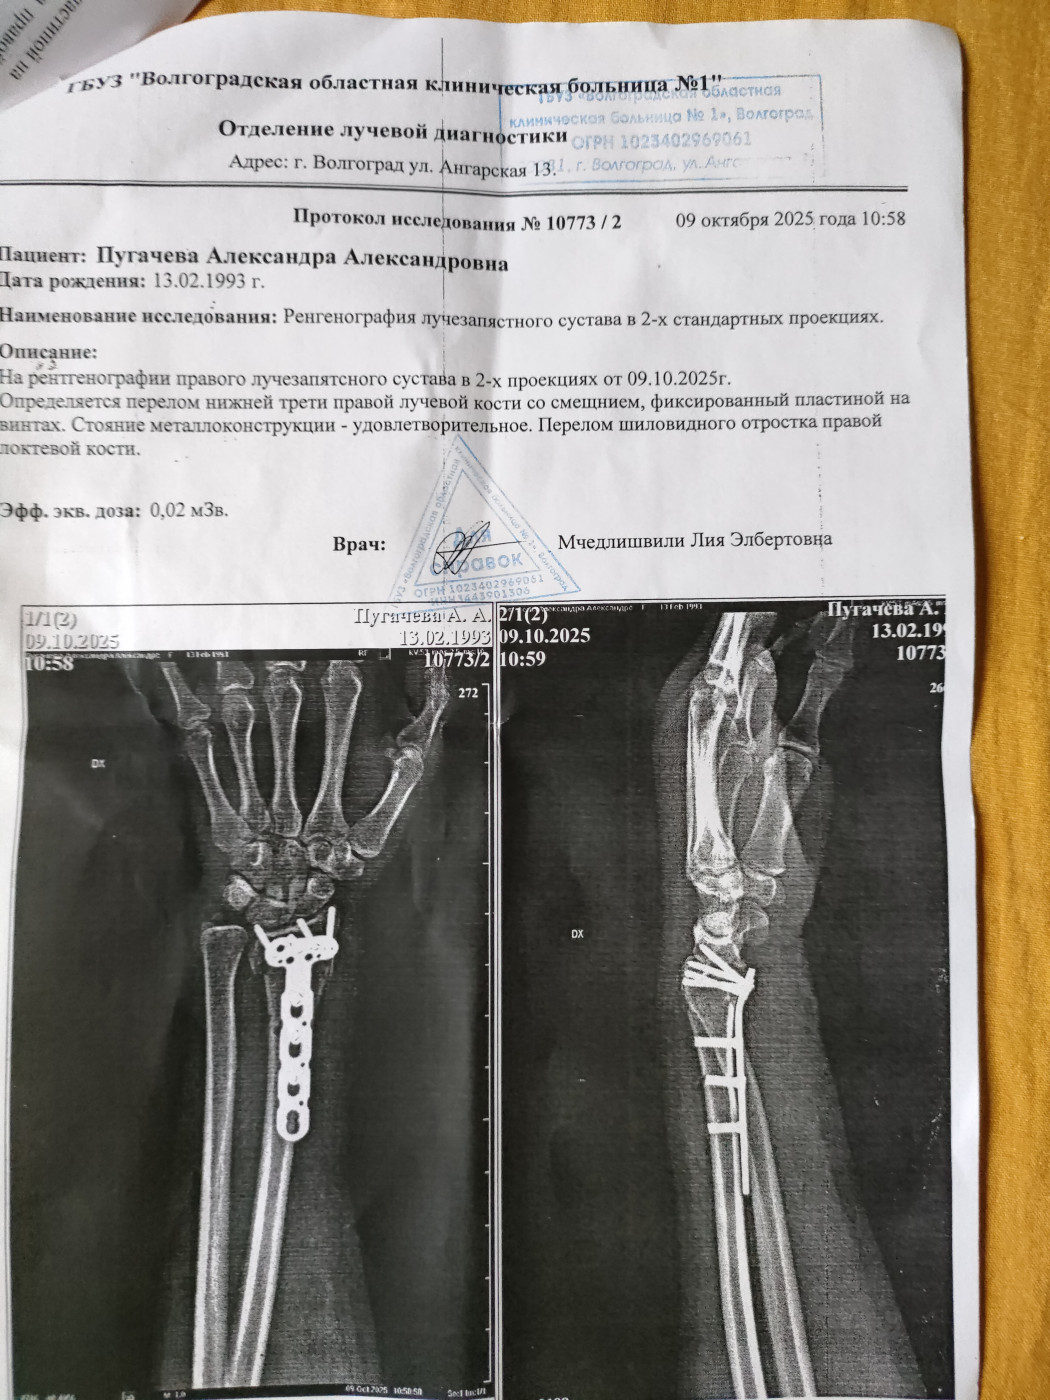

Что это за травма? И как сделать, чтобы меньше болело?

Не поднимается рука вверх, в сторону. Не сгибается в кулак правая кисть